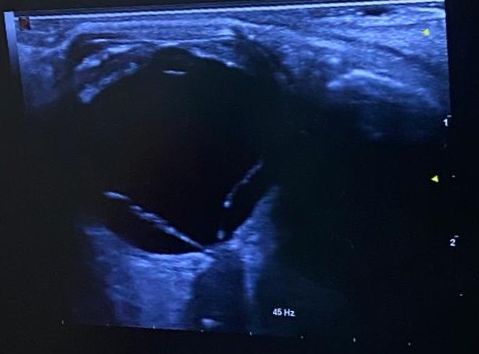

Ecografía clínica ocular: imagen hiperecogénica en V con punto de anclaje en la papila. En estudio Doppler: flujo venoso y arterial.

Juicio clínico: desprendimiento de retina regmatógeno de ojo derecho. El diagnóstico diferencial incluye: desprendimiento de vítreo posterior, oclusión de arteria o vena retiniana, neuropatía óptica isquémica, hemorragia vítrea.